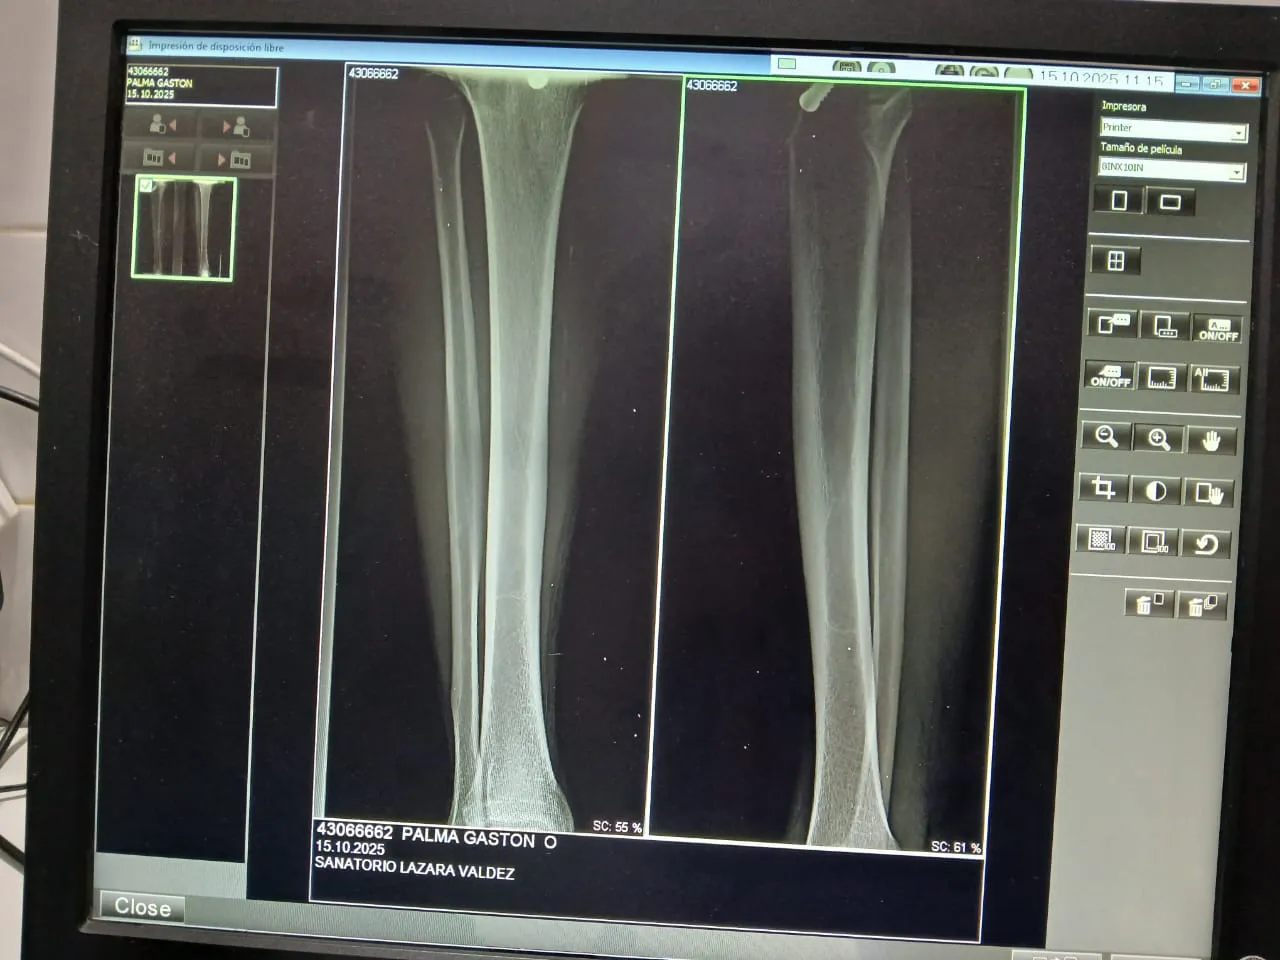

Según el parte emitido por el Departamento de Medicina Legal, Palma fue revisado en su domicilio particular este miercoles 15 de octubre, donde los profesionales constataron una herida de 3 centímetros en la pierna derecha, con tres puntos de sutura y sin complicaciones óseas.

La lesión, producto del proyectil que lo alcanzó durante los disturbios, muestra una evolución positiva, y los especialistas estiman una recuperación completa en menos de 30 días, siempre que no surjan infecciones o complicaciones secundarias.

El propio efectivo informó que una radiografía descartó fracturas, lo que llevó tranquilidad a su entorno y a sus compañeros de fuerza. Actualmente, el Cabo Palma sigue tratamiento con antibióticos y analgésicos, bajo supervisión médica.